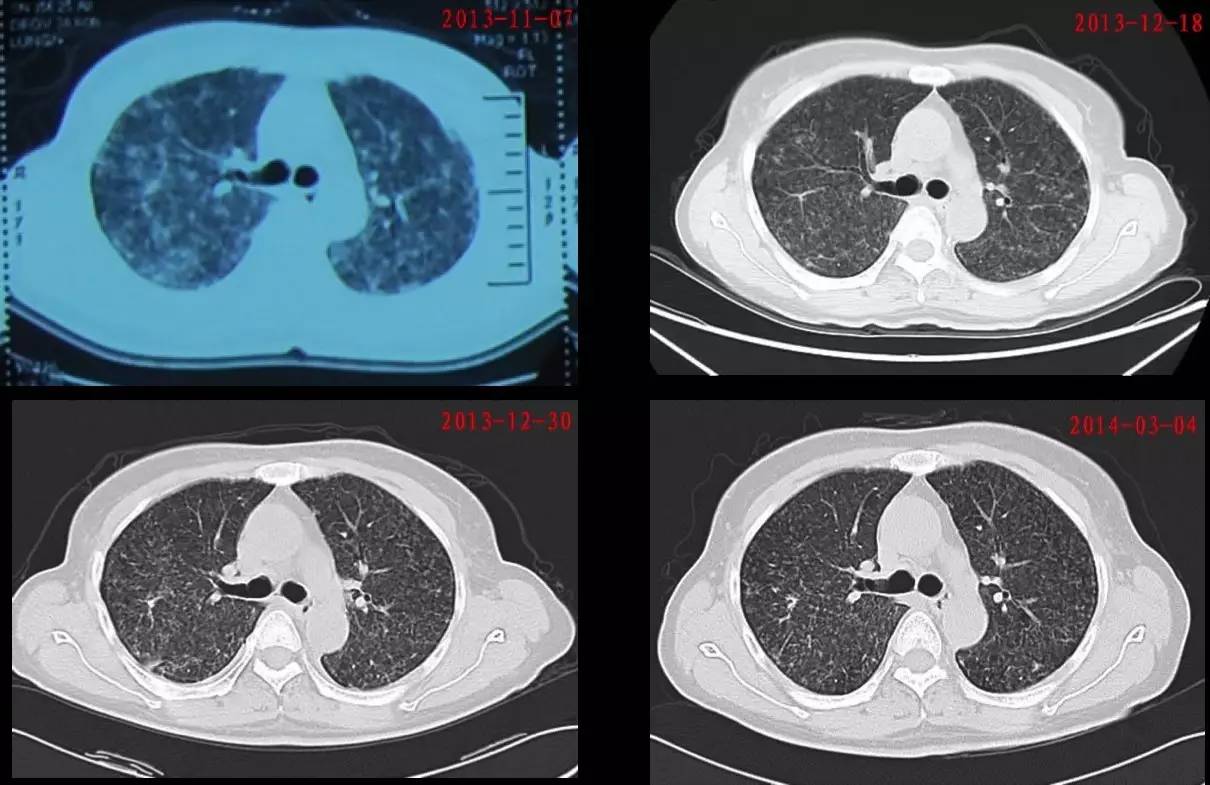

2014-03-04患者返院复查:

1. 胸部CT提示双肺病变较前吸收(图5)。

图 5:该患者治疗前后胸部CT对比

2. 血气分析示:PH 7.43,PaO2 85 mmHg,PaCO2 33 mmHg,BE -1.6 mmol/L,HCO3-23.7 mmol/L,P(A-a)O2 28 mmHg。

3. 肺功能:轻度限制性肺通气功能障碍,气道阻力正常,肺弥散功能轻度下降。

2014年7月毕医师治疗组与患者家属联系得知患者已可下地劳动。